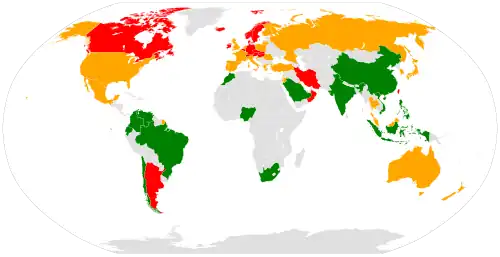

Osteoporosis becomes more common with age, especially after 50 years (its prevalence rises from about 2% at 50 years to almost 50% by the age of 80).[200] It affects women more than men due to the sharp fall in estrogen production that follows menopause.[200] Globally, it is estimated that 21.2% of women and 6.3% of men over the age of 50 have osteoporosis, corresponding to a total of around 500 million people worldwide.[201] About 15% of Caucasians in their 50s and 70% of those over 80 are affected.[7] In the developed world, depending on the method of diagnosis, 2% to 8% of males and 9% to 38% of females are affected.[13] Rates of disease in the developing world are unclear.[14]

In 2019,[204] up to 37 million fragility fractures linked to osteoporosis were thought to occur in people over the age of 55 worldwide.[201] Globally, 1 in 3 women and 1 in 5 men over the age of 50 will have an osteoporotic fracture.[201] Data from the United States shows a decrease in osteoporosis within the general population and in white women, from 18% in 1994 to 10% in 2006.[205] White and Asian people are at greater risk.[3] People of African descent are at a decreased risk of fractures due to osteoporosis, although they have the highest risk of death following an osteoporotic fracture.[205]

It has been shown that latitude affects the risk of osteoporotic fracture.[199] Areas of higher latitude such as Northern Europe receive less Vitamin D through sunlight compared to regions closer to the equator, and consequently have higher fracture rates in comparison to lower latitudes.[199] For example, Swedish men and women have a 13% and 28.5% risk of hip fracture by age 50, respectively, whereas this risk is only 1.9% and 2.4% in Chinese men and women.[205] Diet may also be a factor that is responsible for this difference, as vitamin D, calcium, magnesium, and folate are all linked to bone mineral density.[206]